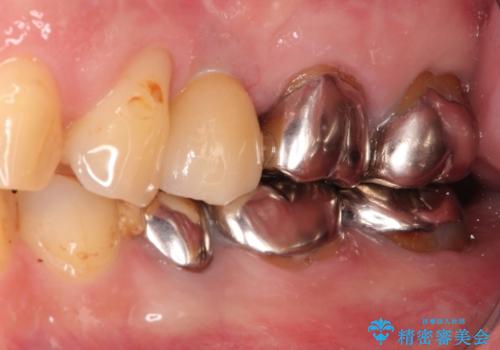

インプラントによる治療は隣在歯を削らずに咬合回復できるという利点があります。

セラミッククラウンにより自然な見た目で修復できました。